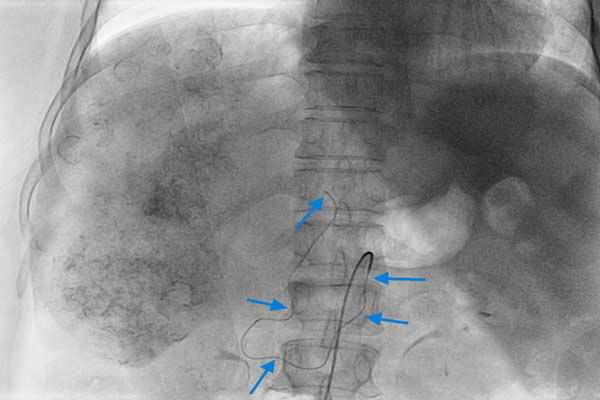

患者,女,62歲,以肝癌肝內(nèi)廣泛轉(zhuǎn)移收住入院,已無(wú)外科手術(shù)切除機(jī)會(huì),只能行介入化療栓塞術(shù)(TACE)。術(shù)中血管造影發(fā)現(xiàn)為肝臟供血的腹腔干已經(jīng)閉塞,導(dǎo)管無(wú)法進(jìn)入肝動(dòng)脈行介入化療栓塞術(shù),介入手術(shù)只能終止。由于已無(wú)其它治療方法,介入化療栓塞術(shù)終止,意味著患者只剩下1-2個(gè)月的生命??吹交颊吆图覍賹?duì)生命的渴望和對(duì)我們介入醫(yī)生的高度信任,我們不甘心就此放棄手術(shù)和延長(zhǎng)患者生命的機(jī)會(huì)。任小軍副主任反復(fù)研究血管造影圖像,見患者腸系膜上動(dòng)脈有側(cè)枝循環(huán)供應(yīng)到肝動(dòng)脈,仍有希望通過細(xì)小迂曲的側(cè)枝循環(huán)繞到肝動(dòng)脈進(jìn)行肝癌化療栓塞術(shù),但路途遙遠(yuǎn),操作復(fù)雜,手術(shù)時(shí)間長(zhǎng),醫(yī)生接受射線輻射大幅增加,并且成功的可能性很小,但是不嘗試,就沒有成功的機(jī)會(huì)。與家屬深入溝通后,任小軍副主任和任雪會(huì)副主任醫(yī)師反復(fù)耐心操作微導(dǎo)管,在技師和護(hù)士的高度配合下,導(dǎo)管終于成功進(jìn)入肝固有動(dòng)脈和肝右動(dòng)脈,對(duì)患者成功實(shí)施了介入化療栓塞術(shù),術(shù)后攝片和CT掃描顯示栓塞的碘油和化療藥大量沉積于肝臟腫瘤內(nèi),持續(xù)殺滅著腫瘤細(xì)胞?;颊咝g(shù)后反應(yīng)輕,恢復(fù)良好,現(xiàn)已出院。

這種腹腔干閉塞,通過腸系膜上動(dòng)脈側(cè)枝循環(huán)治療肝癌的病例少見,它技術(shù)難度大,需要深入插管到腸系膜上動(dòng)脈-回腸動(dòng)脈-胃十二指腸動(dòng)脈-肝固有動(dòng)脈-主要供血的肝右動(dòng)脈,導(dǎo)管在腸系膜上動(dòng)脈內(nèi)反復(fù)操作,出現(xiàn)腸系膜上動(dòng)脈夾層并引起腸梗死的風(fēng)險(xiǎn)大,手術(shù)時(shí)間長(zhǎng),介入醫(yī)生接受射線輻射多,一般都會(huì)終止治療。為了讓患者獲得最佳療效而延續(xù)生命,我們不放棄,敢創(chuàng)新,即使只有1%的希望也要付出100%的努力。對(duì)于一個(gè)醫(yī)生,沒有什么比延續(xù)患者生命更重要,沒有什么比延續(xù)患者生命更令人驕傲和自豪!